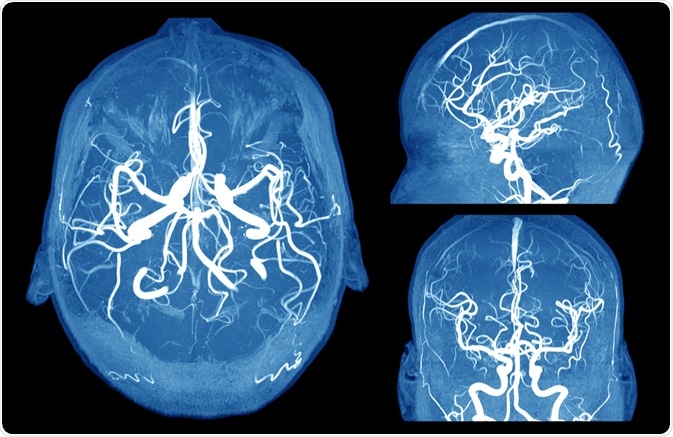

A brain aneurysm is a diseased or abnormal dilatation of the cerebral arteries at a weak spot. These typically thin-walled aneurysmal sacs of blood may continue to enlarge because of the force of the arterial pulsatile flow. A ruptured aneurysm leads to a subarachnoid hemorrhage, an SAH.

Image Credit: MriMan/Shutterstock.com